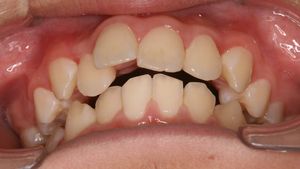

12歳の男の子、前歯がガタガタで出っ歯が気になるので矯正相談に来られました。レントゲン撮影したところ、下顎の第二小臼歯(黄色い丸で囲った部分)が先天的に欠損していて、乳歯がそのまま残っていることが判明しました。両隣りの永久歯に比べて高さが一段低くなっていて、咬み合せに問題があります。このような乳歯はいずれ駄目になって抜歯することになります。今回は、非抜歯矯正を希望されたのでまずはこのままの状態で矯正治療をスタートしました。大学に進学した後に乳歯を抜歯しての再治療を検討するとのことです。